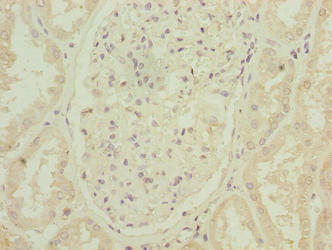

Immunohistochemistry of paraffin-embedded human colon cancer using CSB-PA773801LA01HU at dilution of 1:100

Immunohistochemistry of paraffin-embedded human kidney tissue using CSB-PA773801LA01HU at dilution of 1:100